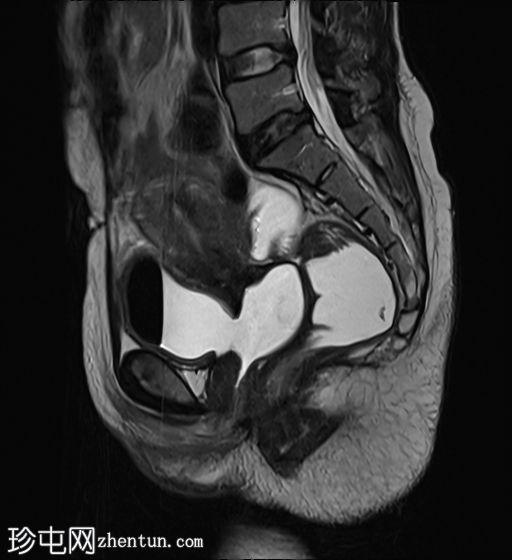

膀胱充盈后

矢状位

T2加权像

膀胱后壁与阴道前壁之间存在宽阔的瘘管。膀胱内可见气液平面。

阴道后穹窿上部与直肠中段前壁之间可见另一条较小的瘘管。在重扫描T2加权像上也可见。

子宫未见局灶性病变。

左侧卵巢可见液性囊肿。

盆腔少量游离液体。

本病例显示了一个医源性膀胱阴道瘘。

此外,还有一个较小的直肠阴道瘘,容易被忽略,但直肠扩张并伴有液体信号强度(未注射凝胶)提示存在直肠阴道瘘。给予患者饮水以充盈膀胱,薄层扫描清晰地显示了狭窄的瘘管。

当膀胱未完全充盈时,直肠阴道瘘不明显,直肠内液体量也很少。然而,膀胱充分充盈后,直肠扩张,瘘管清晰可见。这凸显了在怀疑存在短瘘时,通过注入外源性液体或增加口服液体摄入量等方法确保操作技术正确的重要性,正如本病例所示。